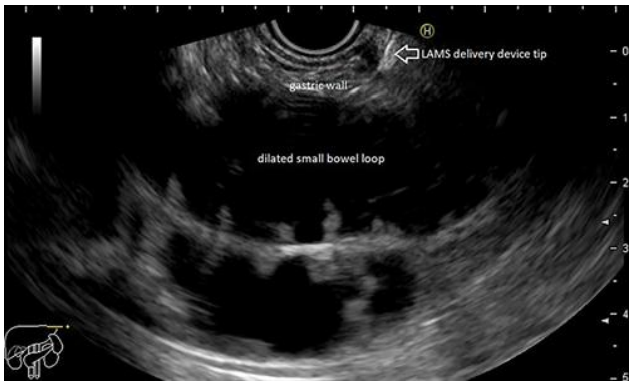

Fig. 1.: Jejunal loop

EUS-GJ involves obtaining access to the jejunum endoscopically and sonographically from the stomach, using a biflanged lumen apposing metal stent (LAMS). This is achieved through a newly formed fistulous tract. Thus creating a gastrojejunal bypass fully endoscopically.

The procedure involved instilling 900 cc of saline solution with methylene blue to promote jejunal dilation using a catheter. Under ultrasonographic guidance, the bowel loop was accessed using a "wireless endoscopic simplified technique" (WEST), placing a lumen-apposing stent (LAMS) through the greater curvature of the stomach. The enteral communication was created and dilated with a through-the-scope balloon up to 15 mm .[3-4]. The patient restarted oral food intake within 12 hours and remained food-tolerant until he passed away, 3 months after the procedure